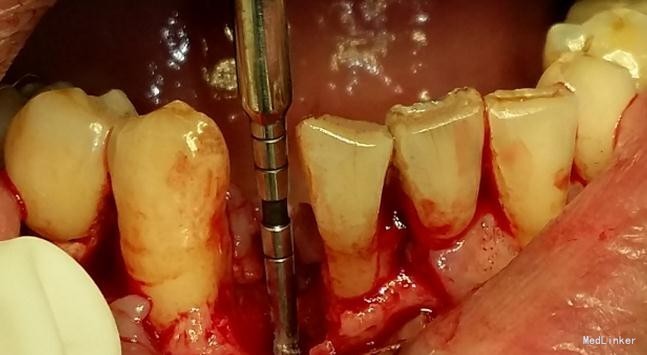

患者,男,45岁,右侧下颌侧切牙严重龋坏,拔除后要求种植修复,平素体质一般,无药物、食物过敏史,无高血压、心脏病等系统病史

牙科CT检查骨量适中,适合种植

种植修复